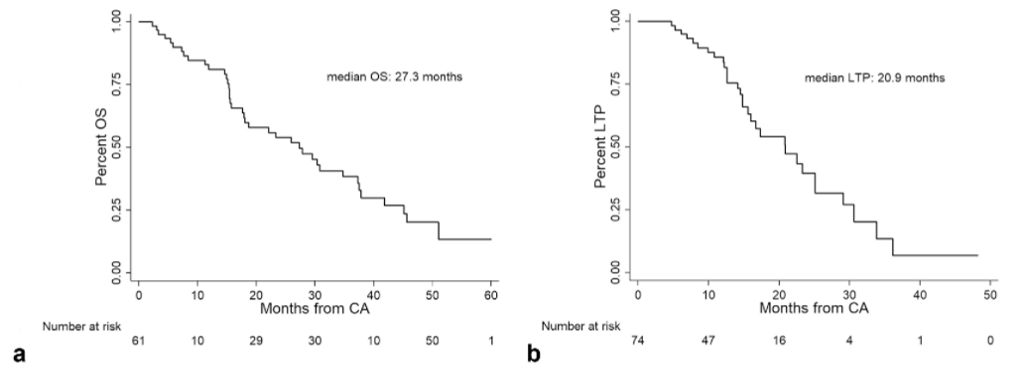

③ 总生存曲线和局部肿瘤进展曲线:冷冻消融后中位生存时间为 27.3 个月,中位局部肿瘤进展时间为 20.9 个月。